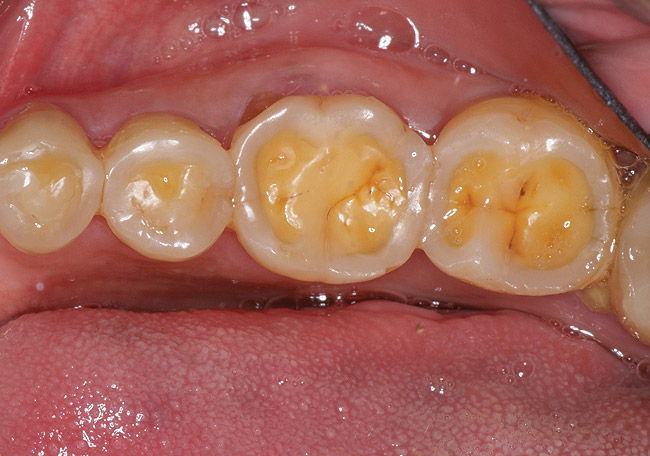

Figure 2  This patient with a history of chronic alcoholism and frequent night vomiting has dissolved the occlsual surfaces of his posterior teeth.

Figure 2

If a patient has risk factors that can contribute to dental erosion, an examination will reveal clinical signs and symptoms of dental erosion. It is unlikely that dental erosion will be seen without other contributing factors. Tooth wear and abrasion typically occur in combination with dental erosion. In the clinical evaluation of tooth surfaces for the diagnosis of erosion, what is typically seen are smooth, shiny surfaces of the teeth where the usual anatomic form of the tooth should be. In patients ingesting very acidic diets, the facial surfaces of anterior teeth are very smooth, and if the beverages being ingested have high sugar content, these teeth may have caries at their facial gingival margins (Figure 1). The occlusal surfaces of posterior teeth in the more advanced stages of erosion due to regurgitation may have extensive exposed dentinal areas with loss of anatomic form (Figure 2). In some cases, the chemical erosion combined with toothbrush–toothpaste abrasion can remove all the enamel, leaving only the dentin exposed (Figure 3). These teeth may exhibit sensitivity. Posterior teeth with restorations may demonstrate fillings that are higher than the surrounding occlusal surfaces of the enamel. Anterior teeth may demonstrate more incisal translucency due to tooth loss at the incisal edge. In patients with the eating disorder bulimia nervosa, who vomit, the hydrochloric acid causes extensive damage to the lingual surfaces of the anterior teeth, where the enamel is lost, leaving exposed dentin (Figure 4).